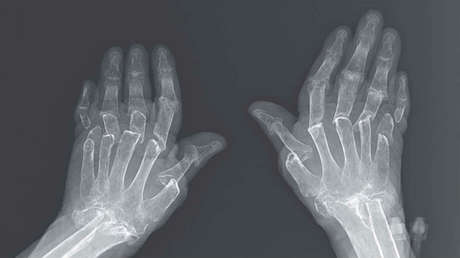

Luego, una imagen por rayos X reveló que la paciente padecía de resorción ósea que afectó a los huesos de sus dedos así como del antebrazo. Se trata de un proceso en el cual los osteoclastos (un tipo de célula implicada en la remodelación de los huesos) destruyen progresivamente el tejido óseo liberando minerales, principalmente calcio, al torrente sanguíneo.

"El fenómeno telescopado es una consecuencia de esta resorción ósea", observaron los autores de la publicación.